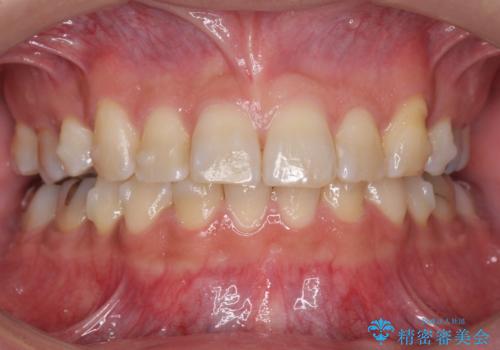

- 前歯だけ歯並びを治したいとのご希望で来院された患者様です。

数年前にワイヤー矯正を行ったものの、少し後戻りしてしまったそうです。

上の前歯が斜めに見えること、犬歯と小臼歯の間の隙間、上下顎前歯のがたつきを治すことをご希望されていました。

気になるのは前歯だけで、奥歯の咬み合わせは気にならないとのことでした。

ご予算と患者様のご希望により、インビザライン・ライト(マウスピース14枚)によるマウスピース矯正を行いました。